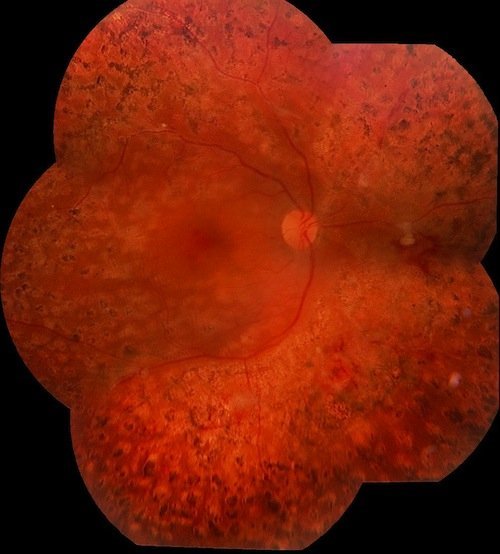

Panfotocoagulación reciente con endolaser.

Panfotocoagulación luego de 1 año.